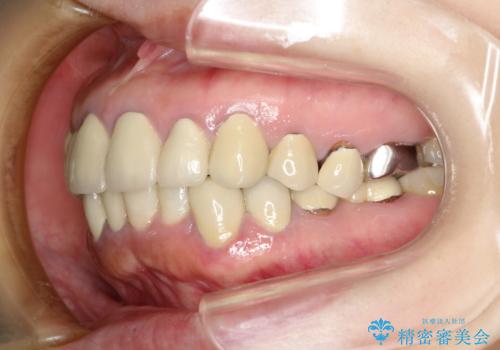

- 下顎の前歯に激痛を覚えて来院された患者様です。

取り急ぎ下顎前歯数歯の根管治療を、銀座しらゆり歯科医院長の林先生にお願いし、それ以外に気になっている、不自然な色調のクラウン、金属部分が見えてブラッシングがしにくいインプラント補綴、口元の突出感、出血のしやすい歯周ポケットなど、全てを解決するための治療を行うこととしました。